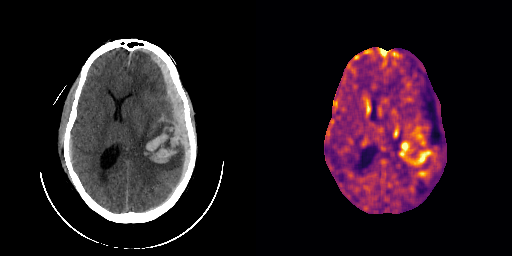

fig:qualitative_ich

ICH

healthy

We show some slices with examples of ICH in \figurereffig:qualitative_ich as well as surface renderings of scans of subjects with cranial fractures in \figurereffig:qualitative_fractures. (As a reference we also included the same examples for the AE in Appendix D in \figurereffig:qualitative_ich_ae.) It is noticeable that the reconstruction error is high where there is an anomaly. The reconstruction error generally seems to continuously depend on the amount of the patch that is anomalous, as the error maps generally seem to be rather smooth.

The performance for the models used for \figurereffig:qualitative_ich and LABEL:fig:qualitative_fractures are shown in \figurereffig:roc_performance. We observe see that the detection of fractures is the more challenging task for our method than the detection of ICH. This might be due to the smaller number of scans available to evaluate it on (see Appendix B). To put these results in context we provided a table with the inter rater agreement on these tasks in Appendix B: The performance in terms of AUROC is around lower than the average raters.